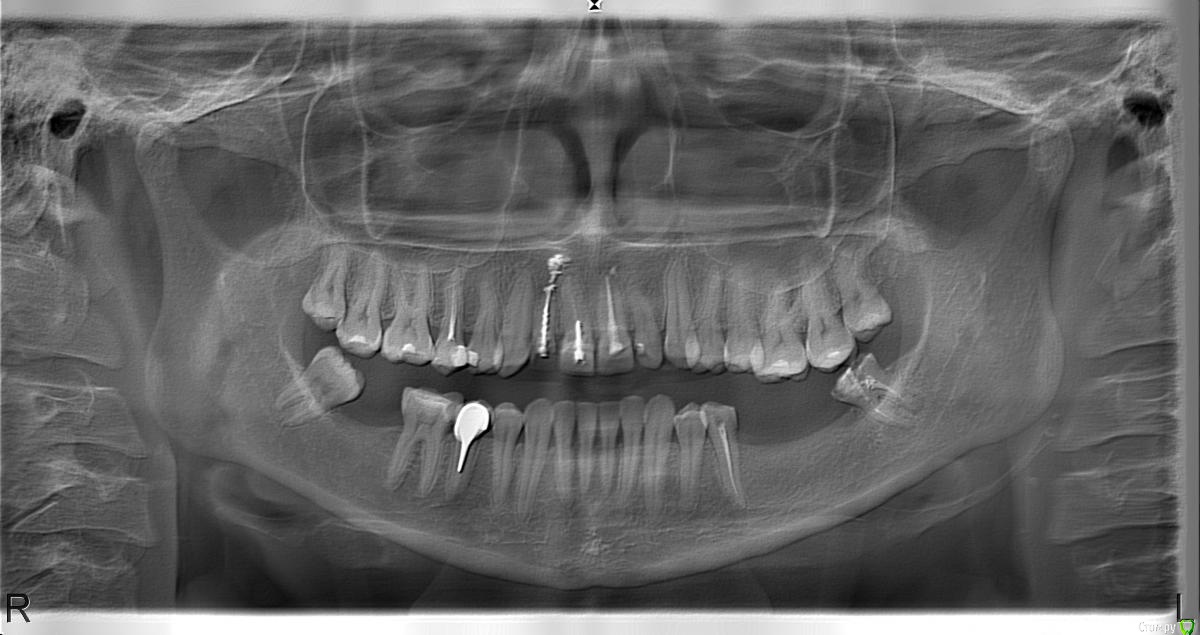

Пожалуйста проконсультируйте по нескольким вопросам, для нас ситуация очень сложная, мнения местных специалистов сильно отличаются. Образ диска кт и панорамный снимок прилагаю.

Жене требуется имплантация 36 и 37, видимо удаление 38, лечение 35.

1. Ставить 2 импланта или возможно лучше 3, и 2 или 3 коронки?

2. Необходима ли костная пластика?

3. Необходимо ли что то делать с выдвинувшимися зубами на ними (26,27), и если необходимо то что именно. стачивать с удалением корней и под коронки, или возможно помочь брекетами?